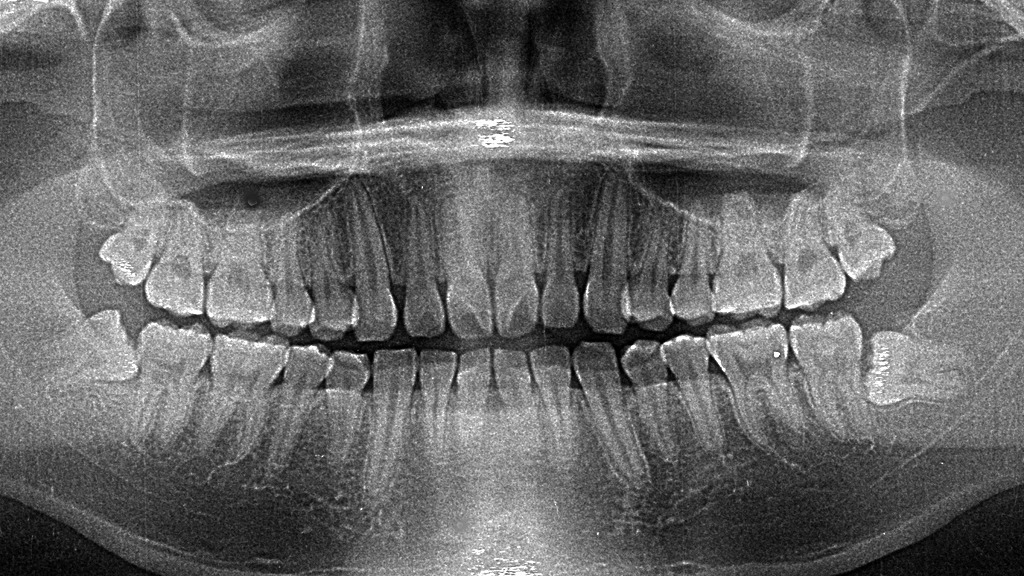

🌐 パノラマ(全体撮影)レントゲン

- 特徴:上下の歯列やあごの骨を一度に撮影

- 用途:親知らずの位置、歯並び、顎関節の状態など広範囲の確認に使われる

- メリット:全体像が分かるので、初診時や治療計画を立てるときに便利

🦷 インプラントや矯正治療の事前検査

- インプラント:骨の厚みや神経の位置を3Dで確認することで、安全な埋入が可能

- 矯正治療:歯並びだけでなく、骨格や歯根の状態を把握して正しい治療計画を立てられる

👉 事前の精密検査を省くと、治療の失敗や後戻りのリスクが増します。